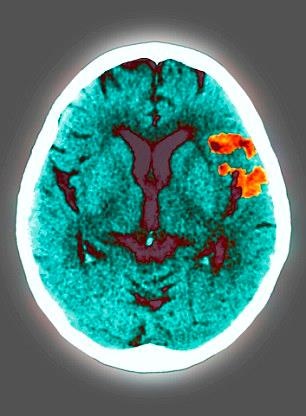

Huyết áp cao được biết đến như là “kẻ giết người thầm lặng” bởi vì nó không có triệu chứng cho đến khi người ta bắt đầu bị các vấn đề về tim hay bị đột quỵ bất ngờ. Đây là một trong những kẻ thù lớn nhất nước Anh.

“Kiểm tra huyết áp là một trong những bước quan trọng nhất mà bạn có thể làm để giảm nguy cơ bị đột quỵ, đau tim hoặc suy tim nhưng rất nhiều triệu người đang bất chấp những rủi ro đối với sức khỏe của họ”.